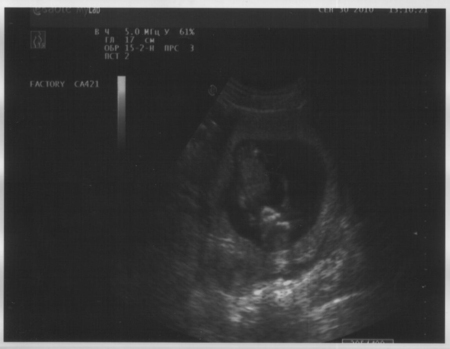

Девочки, сегодня ходили на УЗИ. Это была наша первая встреча... Какое счастье я испытала! Сколько эмоций! Я видела этого маленького человечка, крохотного такого. МОЯ ЖИЗНЬ,МОЕ СЧАСТЬЕ!!!!!

Доктор сказала, что все в норме, плод один, две ручки, две ножки, одна голова. Что развивается по сроку, матка крепкая в норме. Сказала что малыш очень активный

P.S. Срок нам поставили чуть большечем Г 13 неделек (12.2 было)